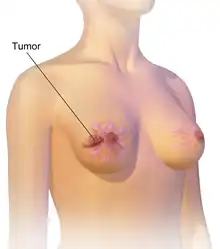

| An illustration of breast cancer | |

Breast cancer is a cancer that develops from breast tissue.[7] Signs of breast cancer may include a lump in the breast, a change in breast shape, dimpling of the skin, milk rejection, fluid coming from the nipple, a newly inverted nipple, or a red or scaly patch of skin.[1] In those with distant spread of the disease, there may be bone pain, swollen lymph nodes, shortness of breath, or yellow skin.[8]